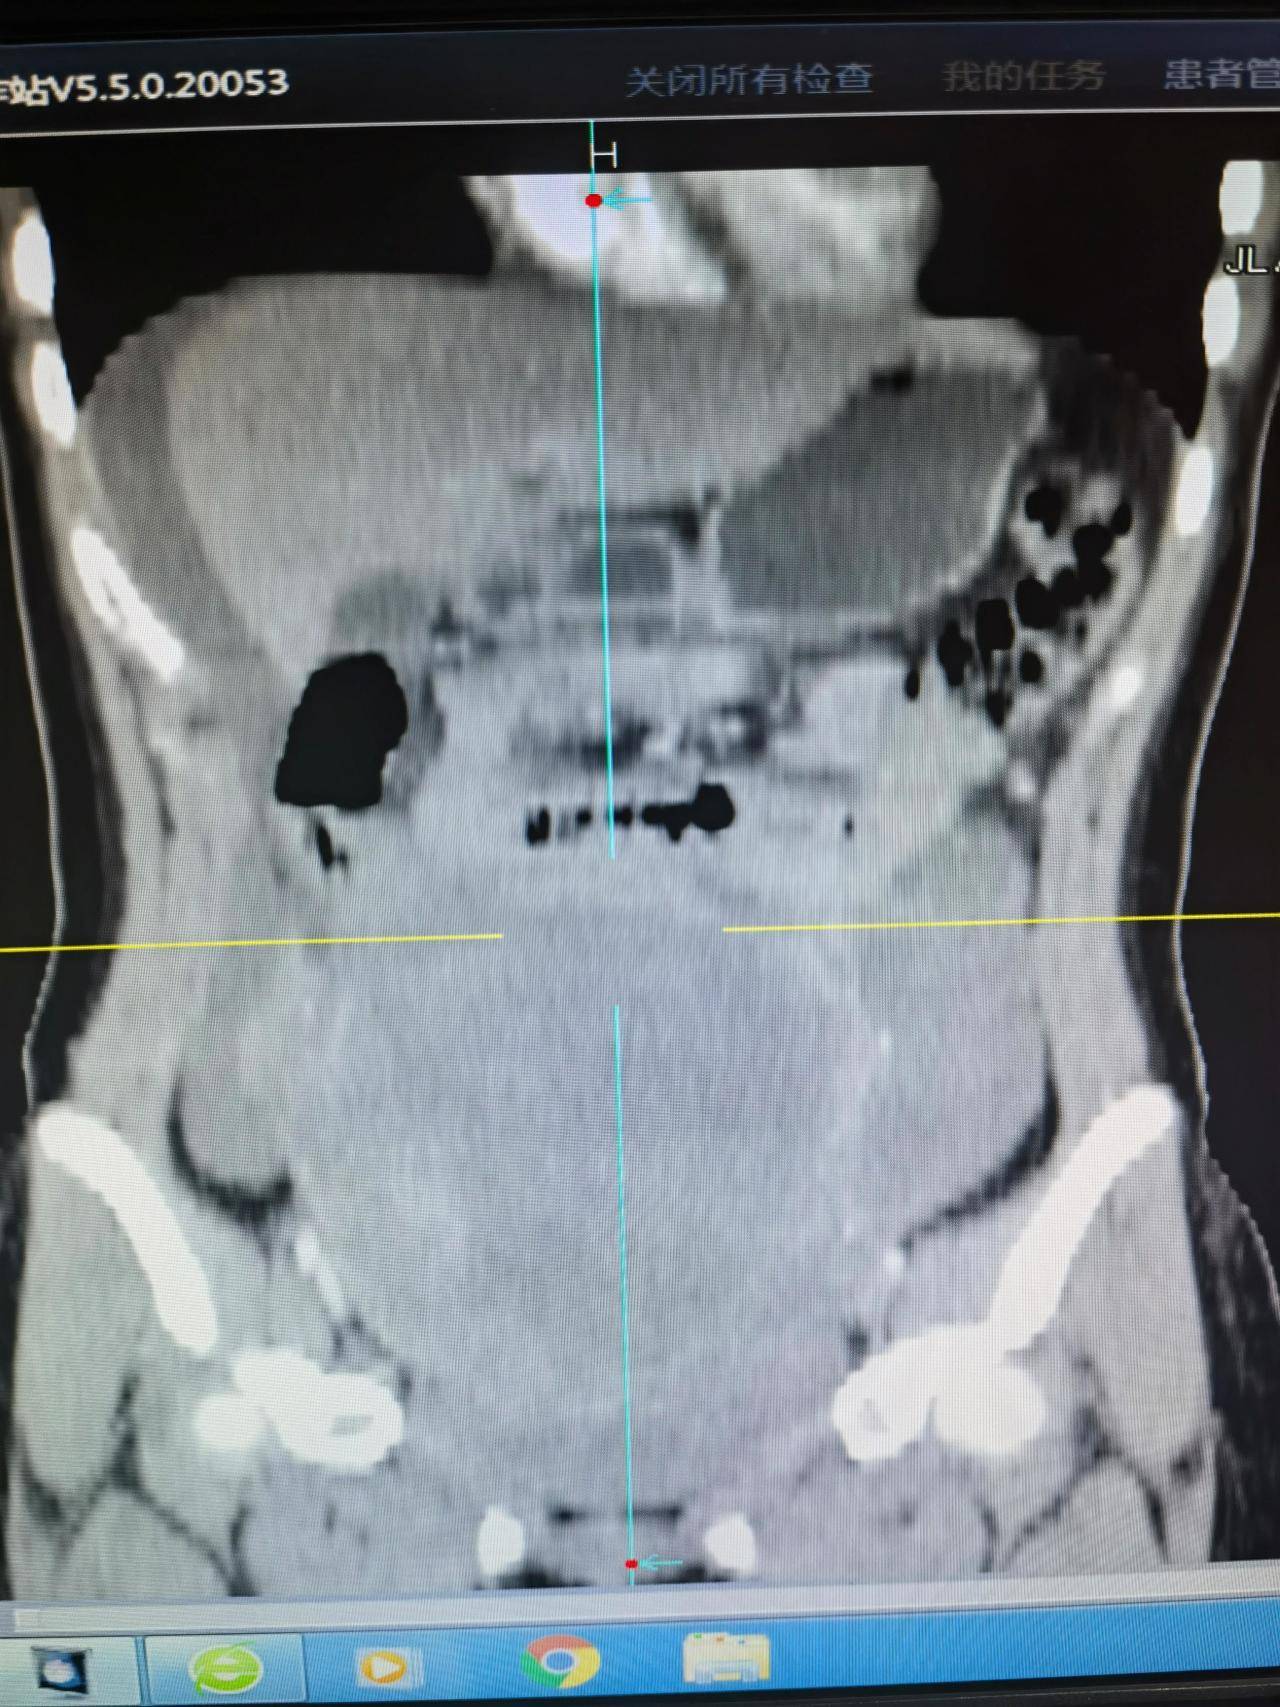

◈ 2023年3月2日,患者来院复查腹部CT提示:中腹部小肠局部见缝合线影,吻合口未见异常强化影,盆腔内见液体密度影。腹腔脂肪间隙稍浑浊,网膜稍增厚。腹壁见瘢痕影。左下腹前腹膜区见小结节影,大小约0.6cm×0.8cm,轻度强化。

◈ 检查诊断:1、符合部分小肠术后,吻合口未见异常强化影。2、盆腔积液,对比前片积液量减少。3、腹腔脂肪间隙稍浑浊,网膜稍增厚,较前片减轻。4、左下腹前腹膜区小结节。

2023年3月2日 腹部CT